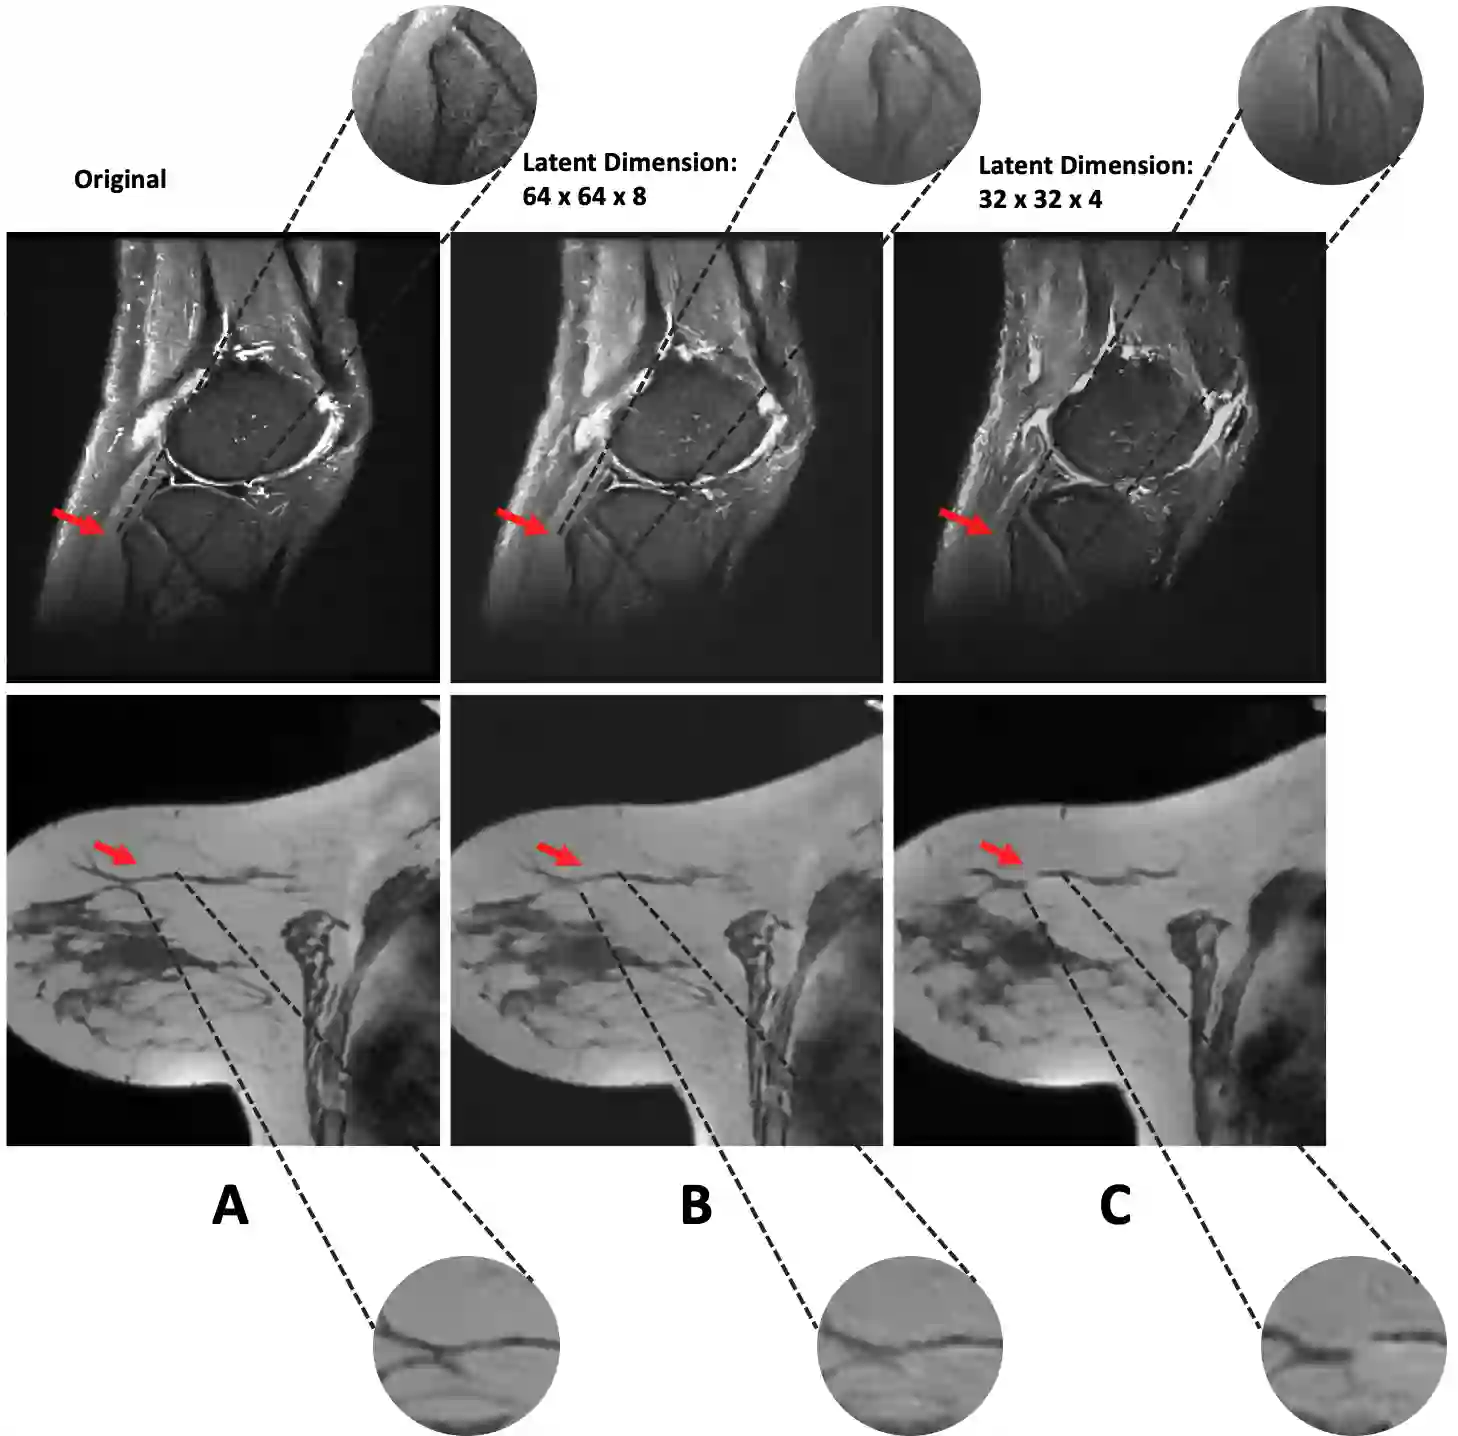

Recent advances in computer vision have shown promising results in image generation. Diffusion probabilistic models in particular have generated realistic images from textual input, as demonstrated by DALL-E 2, Imagen and Stable Diffusion. However, their use in medicine, where image data typically comprises three-dimensional volumes, has not been systematically evaluated. Synthetic images may play a crucial role in privacy preserving artificial intelligence and can also be used to augment small datasets. Here we show that diffusion probabilistic models can synthesize high quality medical imaging data, which we show for Magnetic Resonance Images (MRI) and Computed Tomography (CT) images. We provide quantitative measurements of their performance through a reader study with two medical experts who rated the quality of the synthesized images in three categories: Realistic image appearance, anatomical correctness and consistency between slices. Furthermore, we demonstrate that synthetic images can be used in a self-supervised pre-training and improve the performance of breast segmentation models when data is scarce (dice score 0.91 vs. 0.95 without vs. with synthetic data).